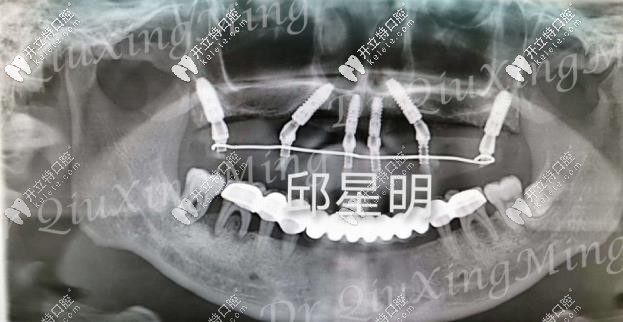

植入種植體的牙片

種植過程也挺快的,大約用了兩個(gè)多小時(shí),六根植體就已經(jīng)植入進(jìn)去了,然后需要等2-3個(gè)月的牙床恢復(fù)期,才能安裝基臺和牙冠。這段時(shí)間只需安心等待就好了!